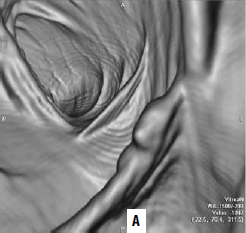

Виртуальная колоноскопия. В последние годы для диагностики опухолей ободочной кишки применяют т. н. виртуальную колоноскопию. Метод представляет собой компьютерное томографическое исследование ободочной кишки после предварительного ее заполнения воздухом. Отличие получаемых результатов от классической КТ в том, что программное обеспечение на основании получаемых с датчиков данных строит трехмерную модель кишки, очень похожую на картину, видимую в обычный фиброколоноскоп (рис. 186). Данное исследование значительно легче переносится больными в сравнении с оптической фиброколоноскопией. Но диагностические возможности метода меньше, чем ФКС: полипы размером менее 1 см не видны.

Рис. 186. А – виртуальная колоноскопия, Б – фиброколоноскопия